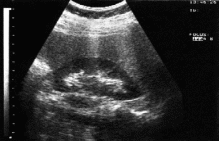

Бүйректің УДЗ

УЗД – оң бүйрек 14,7 х 4,3 см, паренхима қалыңдығы 1,4 см, біртекті, тостағанша-қалқанша жүйесі 1,6 см. Сол бүйрек 10,0 х 4,1 см, паренхима қалыңдығы 1,5 см, тығыздалған. Қорытынды: екі бүйректің өлшемдерінің ұлғаюы. Құрсақ қуысындағы бос сұйықтық.

Бүйректің УДЗ интерпретациялау |

Бүйректердің өлшемі ұлғайған (паренхиманың ісінуі), асцит. |